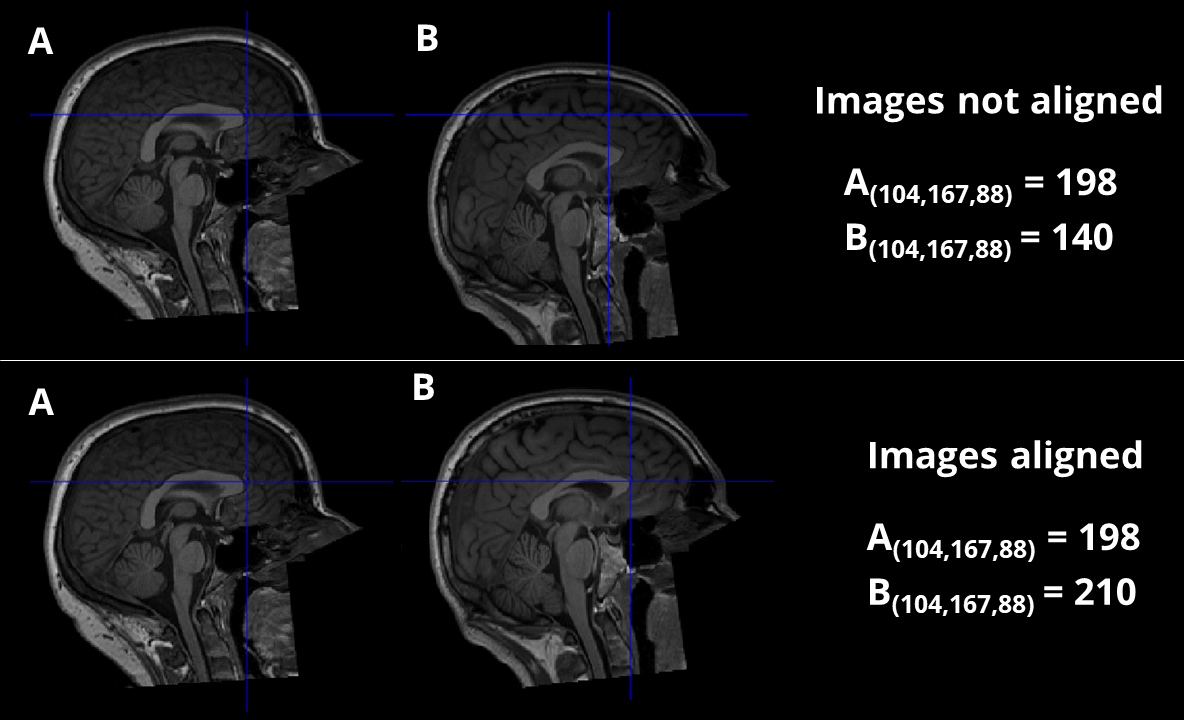

As an example, if we took two structural MR images straight from the scanner and selected voxel coordinates \(\left[104, 167, 88\right]\), it is very unlikely that this voxel would correspond to the same anatomical location in both images. If we were to compare the voxel values from these coordinates across the two images then the comparison would be largely meaningless because of this lack of anatomical agreement. In order for there to be any meaningful connection between images, we need to spatially transform one of them by moving the voxel values around so that the same coordinates correspond to the same anatomical locations. This is illustrated in Fig. 3.

Fig. 3 Illustration of how the same coordinates across two images are meaningless unless there is anatomical alignment between them. In the top row, the images are not aligned and thus the voxel values derived from the same coordinates are not useful because they correspond to different anatomical regions. In the bottom row, the images are aligned and thus voxel values from the same coordinates can be meaningfully compared.#